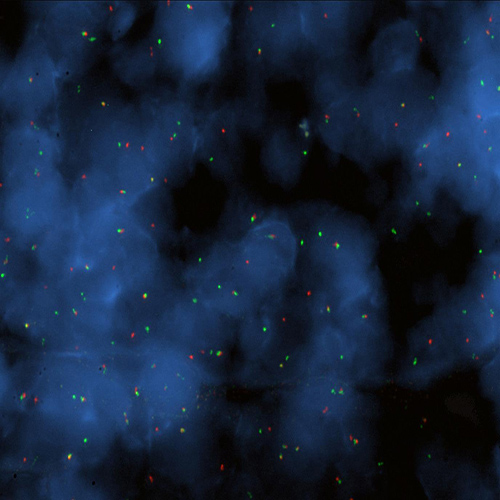

Hybridization of BCL6 break probe to a tissue section showing aberrant pattern (1RG1R1G).

Chromosomal translocations involving band 3q27 with various different partner chromosomes represent a recurrent cytogenetic abnormality in B-cell non-Hodgkin's lymphoma. Kreatech has developed this probe for the specific use on cell material (KBI-10607), or on tissue (KBI-10730). Two different breakpoint regions have been identified; the major breakpoint region (MBR) is located within the 5' noncoding region of the BCL6 proto-oncogene, while the atypical breakpoint region (ABR) is located approximately 200 kb distal to the BCL6 gene. The BCL6 (3q27) Break probe is designed to flank both possible breakpoints, thereby providing clear split signals. The BCL6 (3q27) Break probe is optimized to detect translocations involving the BCL6 gene region at 3q27 in a dual-color, split assay on paraffin-embedded tissue sections.